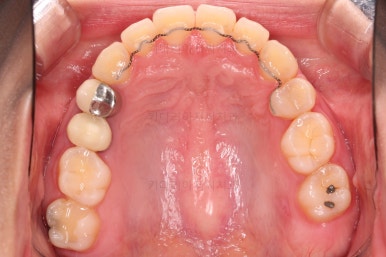

초진 시 입안의 모습을 보실게요.

결국은 앞니 사이에 틈이 생겼기 때문에 이같은 문제점을 인지하시고 내원하셨던거죠.

이번 환자분의 경우는 치아 결손 부위의 잇몸뼈도 양호했고 공간도 그리 크진 않았으며 윗니는 갯수가 1개 부족해도 교합을 맞추는데 문제가 거의 없기 때문에 시간이 좀 더 들더라도 임플란트 없이 앞니 사이 틈과 결손부위 틈새를 모아보기로 했어요.